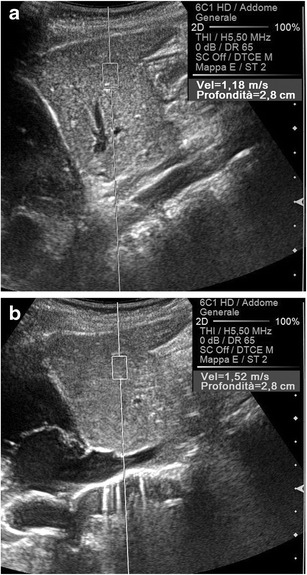

The most important anatomical factor, however, is anisotropy, which reflects the direction dependence of certain properties that some organs demonstrate (Fig. 8). Most of the current knowledge about the effects of anisotropy on the transmission of shear waves derives from an experimental work by Gennisson on an animal model using supersonic shear waves imaging [9], a variant of the ARFI technique in which the pulses generating the shear waves move more quickly in tissues.

A marked anisotropy is normally present in the renal medulla, where—within a given renal segment—Henle loops and vasa recta are parallel to each other, all being oriented from the capsule to the papilla (Fig. 9); the same does not happen in the cortex, mostly occupied by glomeruli and by convoluted proximal and distal tubules, with all of these structures approximately spherical in shape. If the main US beam is sent parallel to a renal segment, it generates shear waves travelling perpendicular to the spatially oriented medullary structures, and then encountering multiple interfaces that decrease their speed of propagation, which results in apparently lower elasticity values (Fig. 9). On the contrary, a main US beam perpendicular to Henle loops and vasa recta gives rise to shear waves parallel to such structures and then hindered by much fewer interfaces (Fig. 9), with consequent higher apparent elasticity [9]. In the model of Gennisson, the mean variation of the apparent shear modulus due to the medullary anisotropy was as high as 31.8 % [9], which is consistent with the 40 % fractional anisotropy demonstrated in the renal medulla with diffusion-Magnetic Resonance (MR) [10]. Moreover, a significantly higher speed of shear waves travelling parallel than perpendicular to spatially oriented anatomical structures was observed in muscles [11], in the myocardium [12], and in the brain [13].

Fig. 8.

Schematic representation of an isotropic and an anisotropic object: in the latter, properties vary in the different planes. The term comes from ancient Greek words “ἄνισoς” and “τρoπή”

Fig. 9.

Effect of anisotropy on the speed of propagation of the shear waves. When the axis of the main US beam is parallel to the orientation of the vasa recta and Henle loops (orange box in a), the shear waves travel perpendicular to these structures and then move slowly (2.52 m/s in b). In the opposite condition (blue box in a), the SWV is higher (3.99 m/s in c)